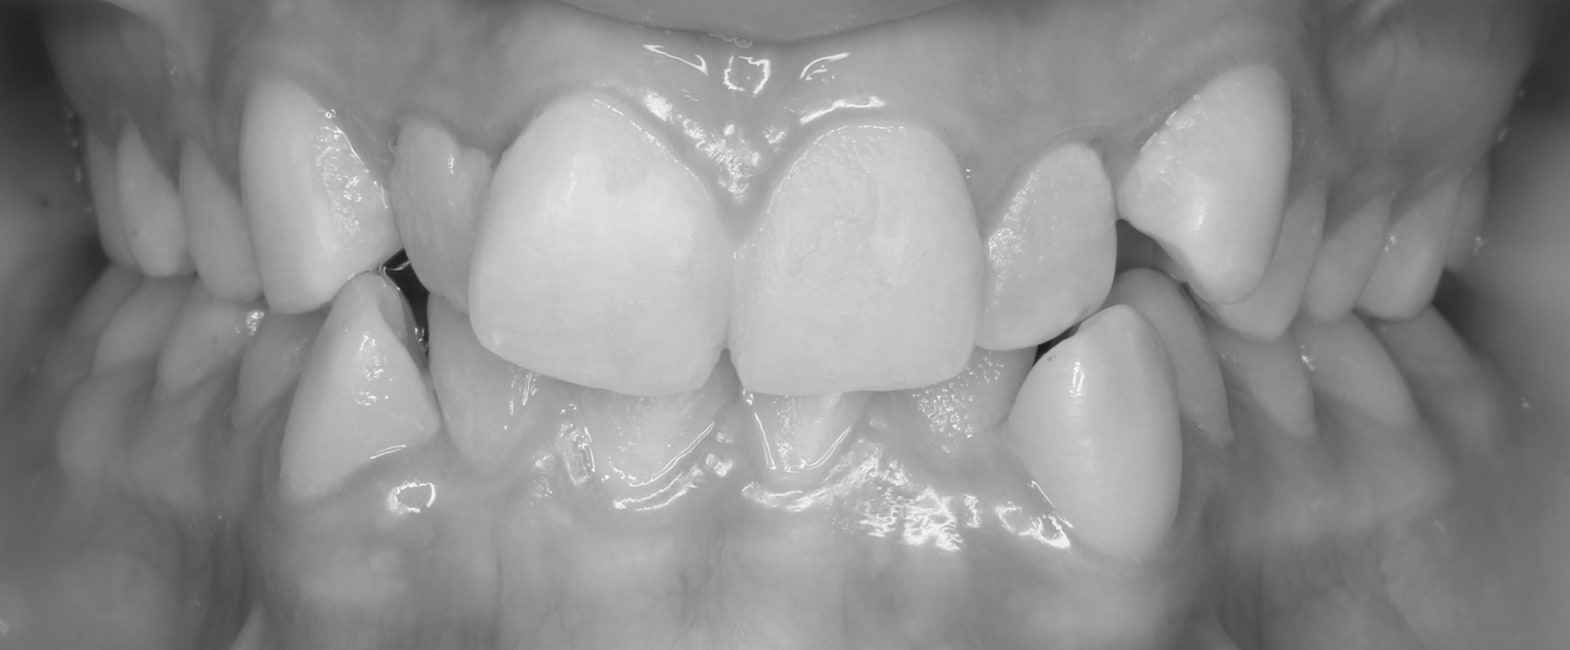

Before

After